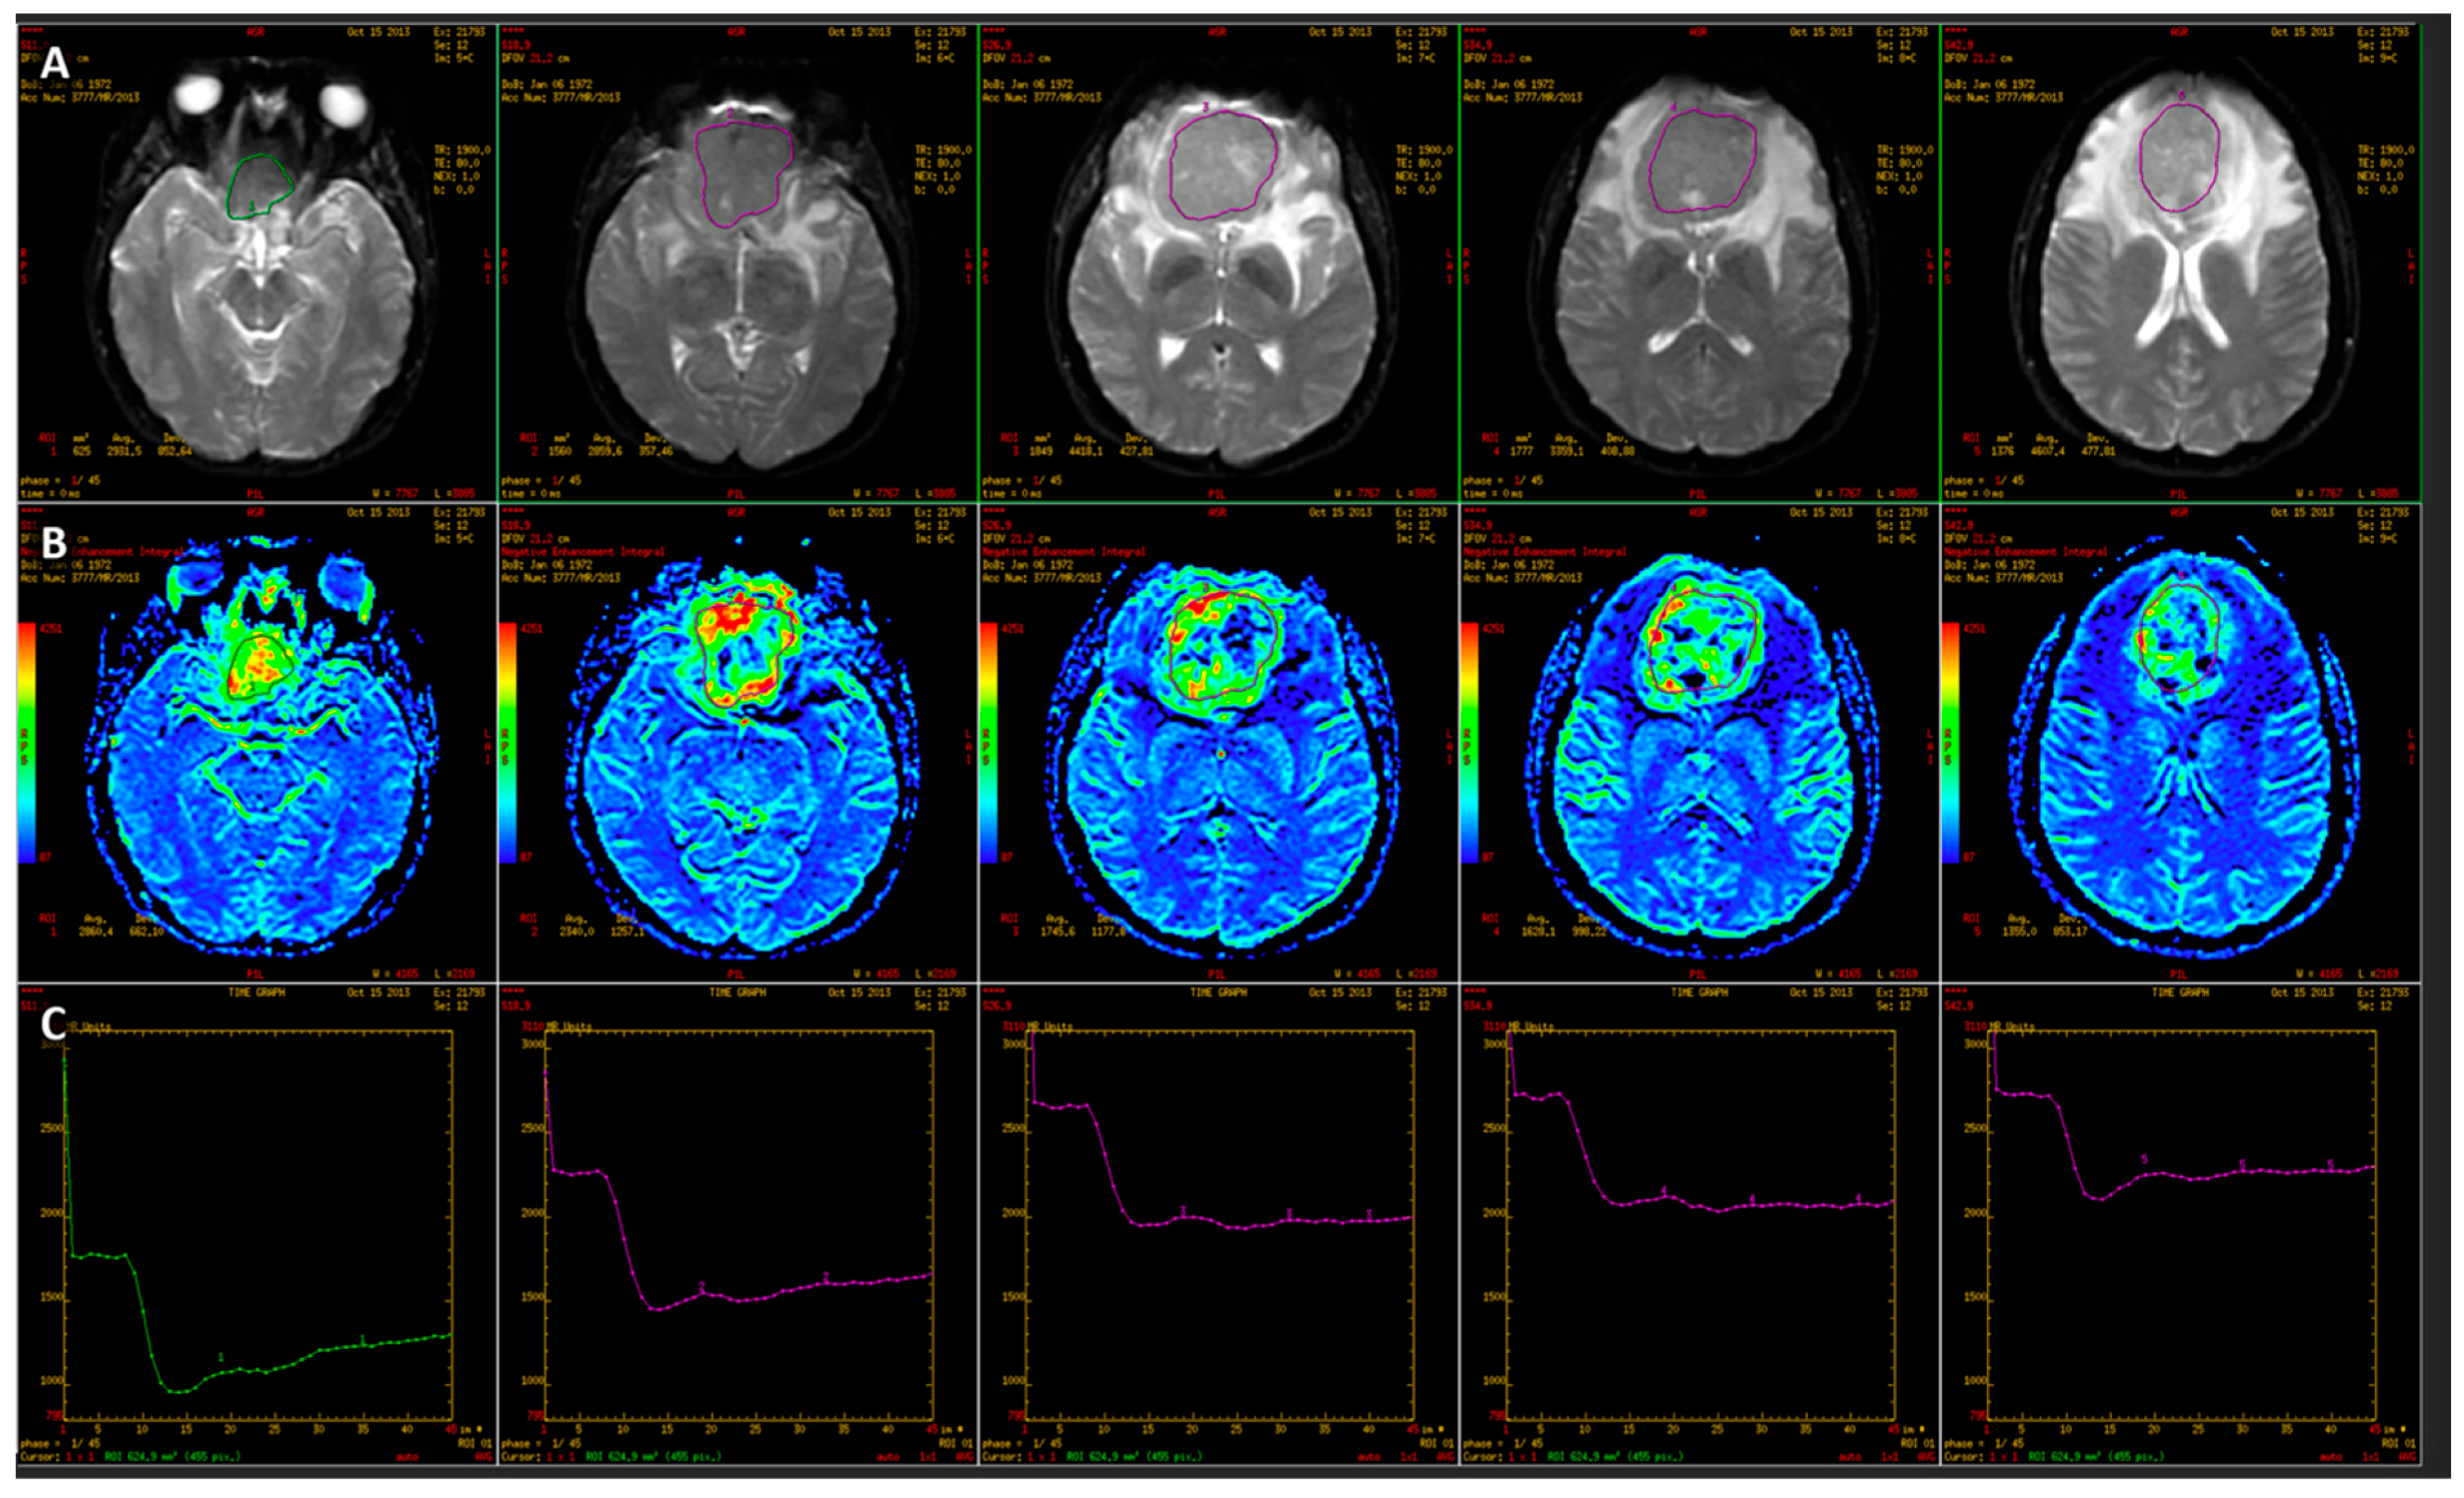

- Bladowska, J.; Zimny, A.; Guziński, M.; Hałoń, A.; Tabakow, P.; Czyż, M.; Czapiga, B.; Jarmundowicz, W.; Sąsiadek, M.J. Usefulness of Perfusion Weighted Magnetic Resonance Imaging with Signal-Intensity Curves Analysis in the Differential Diagnosis of Sellar and Parasellar Tumors: Preliminary Report. Eur. J. Radiol. 2013, 82, 1292–1298. [Google Scholar] [CrossRef]